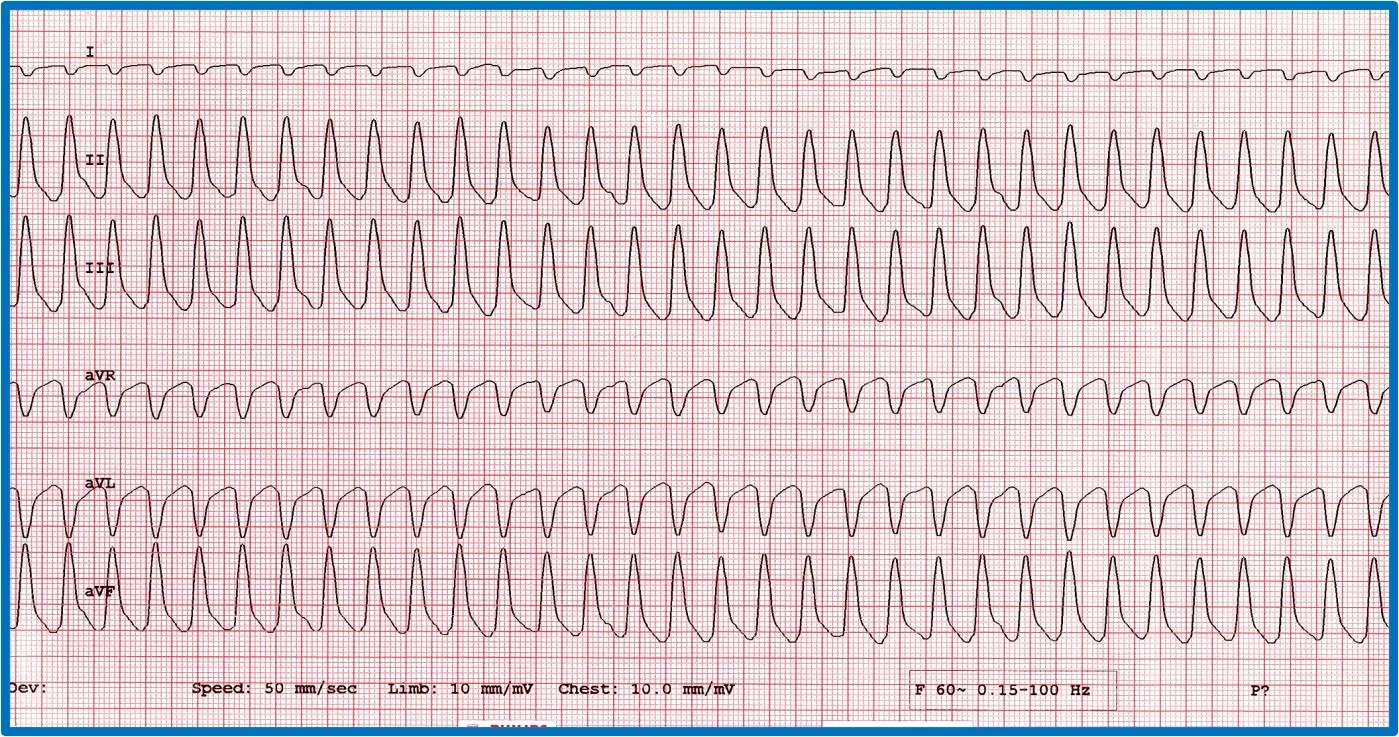

It is important to discern whether the arrhythmia is causing hemodynamic compromise by evaluating peripheral pulse quality, mucous membrane color, patient behavior, and arterial blood pressure. Sustained VT at a high rate is more likely to cause hemodynamic compromise than VT at a slower rate or AIVR (Figure 10). Determining whether the arrhythmia is likely to degenerate into ventricular fibrillation, which causes sudden death, is also important. Increased speed of VT or ventricular ectopic beats increase the likelihood that a beat will fall within the vulnerable period and induce ventricular fibrillation (ie, R on T phenomenon).

Two versions of ventricular runs of ectopy. (A) ECG showing a run of sustained true VT with a rate of 320 bpm in a boxer. (B) ECG showing an AIVR rhythm (ie, slow VT) in a crossbreed dog hit by a car and experiencing traumatic myocarditis. The rate is 180 bpm and not hemodynamically compromising the patient. A sinus beat occuring at the same time as a ventricular beat, causing a fusion beat (circle), can be seen.